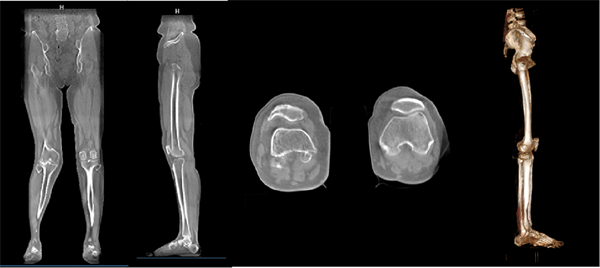

其二:【全】具备全身骨与关节应用。能支持负重位状态下的全脊柱、全下肢,以及单部位(含颈椎、腰椎、髋关节、膝关节、踝关节、气道等)的三维扫描成像,准确反映人体承重情况下的关节状态。对于脊柱侧弯这种三维畸形来说,负重位二维平片只能够提供冠状面影像信息,不同的椎体空间扭转情况在二维平片上可能会呈现相同的投影,影响诊疗;卧位三维成像方式,无法呈现患者真实状态下脊柱形态,同样无法为患者提供精准诊疗;而负重位锥束CT就可以弥补现有影像设备的不足,为患者提供负重位状态下的全脊柱影像,辅助脊柱侧弯精准诊疗。同样对于下肢膝骨关节炎来说,负重位三维成像可以提供负重矢状面三维影像信息,辅助膝骨关节炎患者精准诊疗。

(【全】——负重位全下肢影像图)